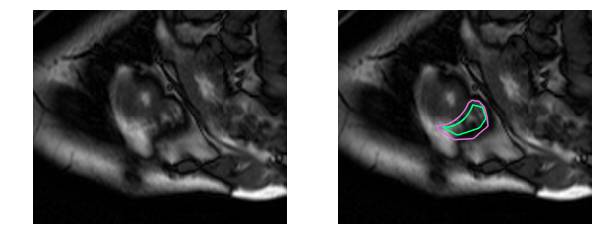

撇开医学术语不谈,要识别RV就更困难了。左心室是一个厚壁圆环,而右心室是一个形状不规则的物体,有薄的壁,有时会与周围的组织混合在一起。这是MRI快照右心室内壁和外壁(心内膜和心外膜)的手工绘制轮廓:

这是一个分割起来很容易的例子。这一个比较困难: